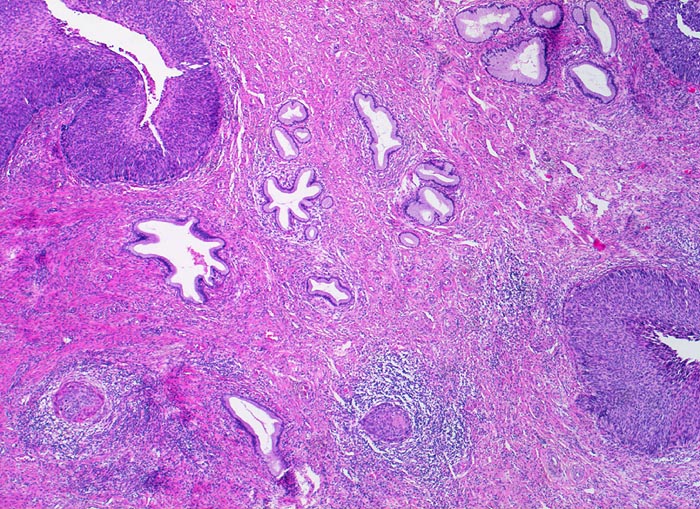

PathoPic ID 3434 - Mikroinvasives Plattenepithelkarzinom, ausgedehntes Cis

Mikroinvasives Plattenepithelkarzinom, ausgedehntes Cis

maligner Tumor

Zervix

Genitalorgane, weiblich

Carcinoma in situ des metaplastischen Plattenepithels in der Umwandlungszone.

Stromainvasion.

PAP V, HPV high risk Typen

Histologie

Vergrösserung

25

Alter

60